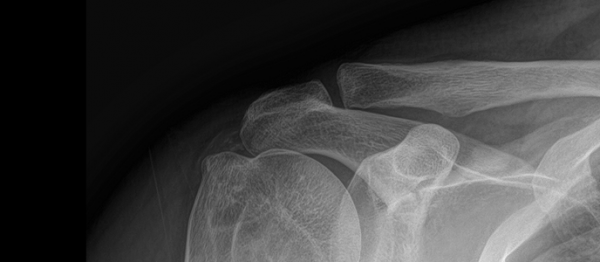

석회쇄석흡인술 페이지 정보 작성자최고관리자 등록일 2025-02-25 17:45 조회30 본문 치료 증상 자고 나서 팔을 들기 힘들 정도의 심한 어깨 통증 나이 / 성별 45세 / 남성 치료내용 석회쇄석흡인술 후 호전 치료기간 2024-09-12 ~ 2024-12-18 null 목록 이전글석회쇄석흡인술 25.02.26 다음글석회쇄석흡인술 25.02.25 댓글 0 댓글목록 등록된 댓글이 없습니다.